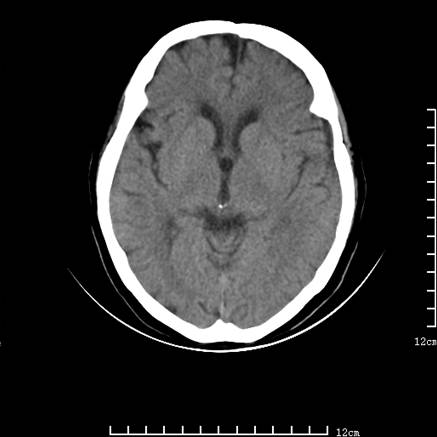

标题: V0514:女,72岁,偶有头晕,自诉记忆力减退,来诊。 [打印本页]

标题: V0514:女,72岁,偶有头晕,自诉记忆力减退,来诊。

1、考虑垂体腺瘤。

2、脑萎缩ct表现。

垂体腺瘤可能性大!另:轻度脑萎缩!

考虑垂体腺瘤可能性大。脑萎缩。